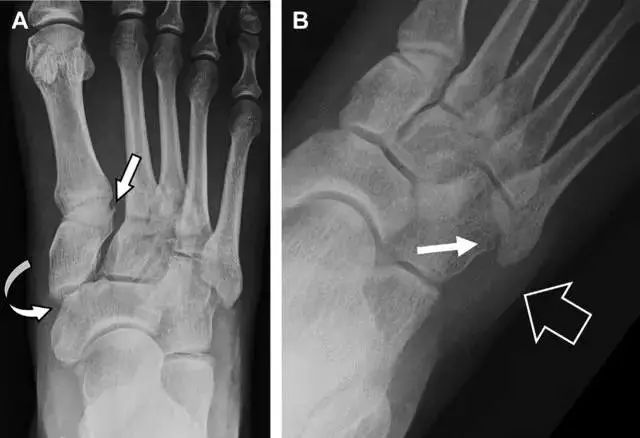

单纯肱骨大结节骨折

与其它肱骨近端骨折不同,单纯肱骨大结节骨折常发生于年轻人。肱骨大结节骨折常由撞击或剪切/撕脱损伤所致:

撞击包括直接撞击、肩峰撞击、上关节盂撞击(极度外展时);

剪切/撕脱损伤常发生于肩关节前脱位。

在常规前后位片上,大结节与肱骨头重叠,骨折不易发现,外旋位前后位片有助于诊断。

图 1 大结节骨折。(A)脂肪抑制序列斜冠状位 MRI,显示肱骨大结节线性骨折无移位(箭头)与周围骨水肿;(B)外旋位前后位(AP)片,证实大结节骨折(箭头),典型的骨折愈合过程中的骨吸收表现;(C、D)初诊时内旋位、外旋位前后位片,初诊时漏诊,仔细回顾影像,内旋伞下可见双密度影(椭圆),骨皮质中断(箭头)。

24

无移位的桡骨头/颈骨折

多发生于摔倒时,手掌撑地,受到轴向、外翻应力所致。常规的前后位片容易漏诊,常需加拍内斜位、外斜位、桡骨头-肱骨小头位片。后脂肪垫可见(位于鹰嘴窝内,一般不可见)和/或前脂肪垫抬高常提示骨性损伤。

图 2 桡骨头骨折。前后位(A)和侧位(B)片示后脂肪垫抬高(黑色箭头),前脂肪垫抬高(白色箭头),呈「帆船征」,其它表现正常;外斜位(C)和桡骨头–肱骨小头位(D)示桡骨头关节内骨折线(虚线黑箭头)累及桡骨颈(虚线白箭头)。